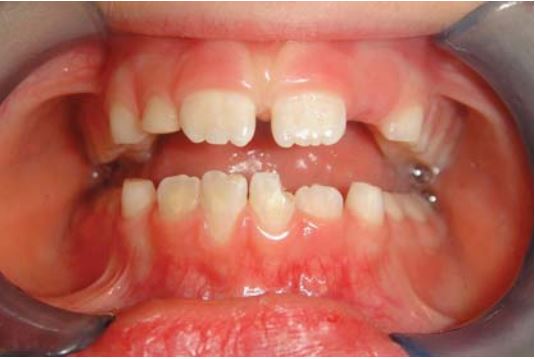

Sau khi răng cửa bị gãy thì nên giữ lại phần gãy trong nước hoặc khăn giấy ẩm để tránh mảnh răng bị khô, gây mất thẩm mỹ và khó kết dính (Sharmin, 2013) (H18.2).

Gắn lại mảnh gãy răng cửa hàm dưới thường khó vì kích thước rất nhỏ (H18.14).